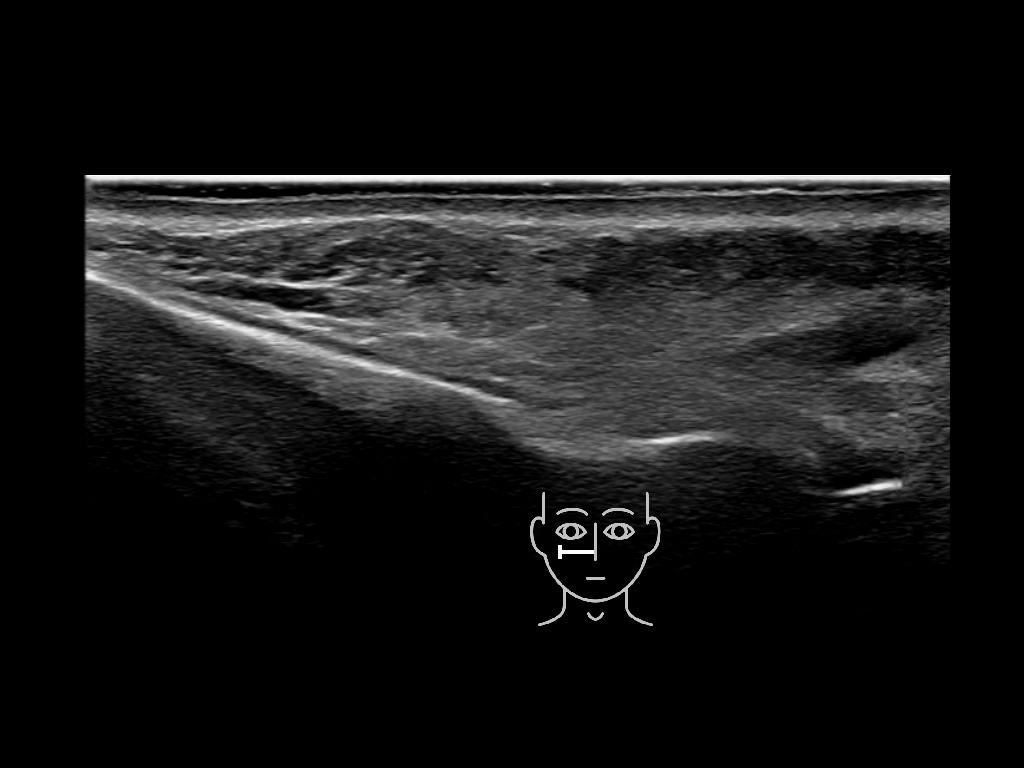

Fascia

Filler deposits may end up unintentionally in the SMAS or fascial layers of the skin. Very often this will not lead to adverse events, however, adverse events ( nodules, migration / redistribution impaired muscle movement and smiling and malar edema) are are often related to filler ending up in the SMAS or fascia.

Hover over an image to view the secondary image or click on the image title for more information.